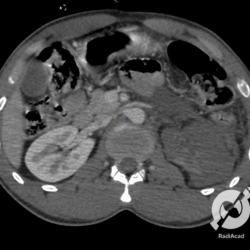

O paciente aqui tem uma imagem hipoatenuante com mais de 3,0 cm no polo inferior do rim esquerdo, com uma coleção líquida perirrenal relacionada a um hematoma. Trauma renal grau 03.